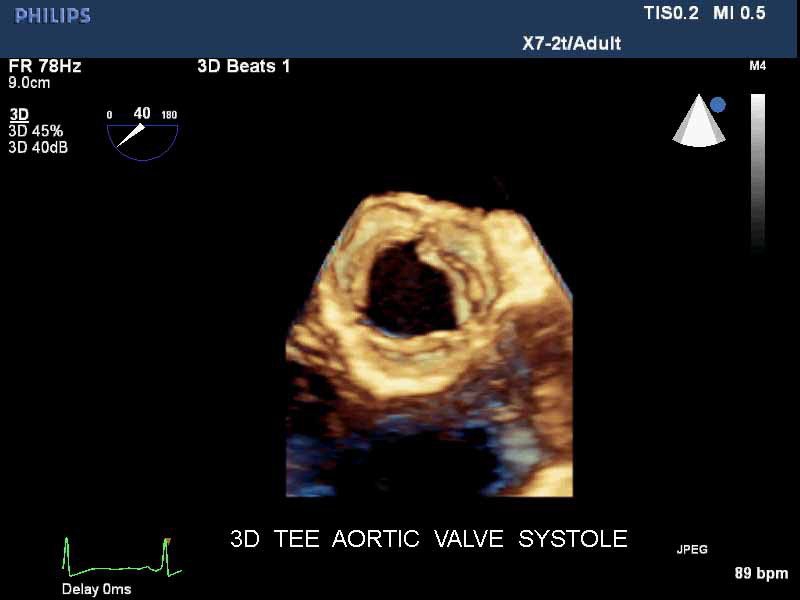

• Чреспищеводная эхокардиография

• Live 3D TEE: Эта функция позволяет проводить чреспищеводную эхокардиографию в режиме реального времени, что позволяет оценить механические сокращения сердца с точностью, необходимой для оценки результатов хирургического вмешательства.

• 3D эхо-кг в реальном времени (Live3DEcho): Эта технология позволяет получать объемные 3D изображения сердца в режиме реального времени.